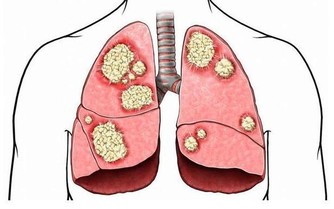

輕微缺乏維生素B2人體不會有任何感覺,但到一定程度時就會出現明顯的症狀,首先,在人體最薄弱的地方,通常是消化道的首尾兩端,即口腔或肛門的局部,出現充血、腫脹,隨後皮膚或粘膜出現潰瘍,然後開始出血,這即是口腔潰瘍和痔瘡。如果長期缺乏維生素B2,那麼人體其它部位也會出現同樣的症狀。

主要原因在於血管,構成血管壁的細胞離不開維生素B2,當缺乏維生素B2時,血管壁(主要是毛細血管,管壁本身就很薄)開始變薄,在血壓的作用下,血管開始向外凸起,當局部的血管都開始鼓起時,就形成了腫塊,最後血管開始裂開出血,如果發生在腦部,你猜到了嗎?對,這就是腦溢血。